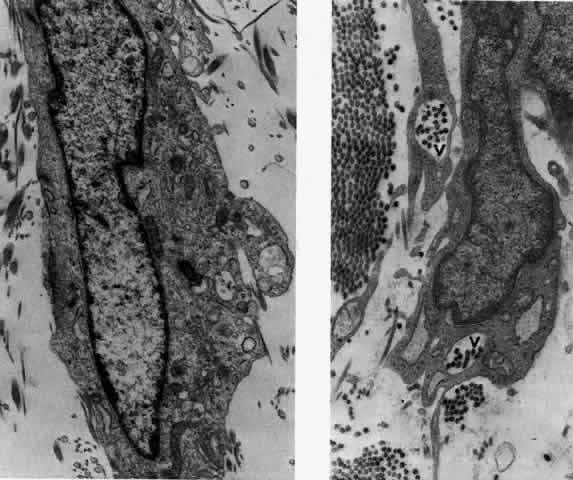

What is clinically represented solely by inflammation and edema is histopathologically a granulomatous lesion of the sclera, the center of which consists largely of plasma cells, lymphocytes, and mast cells (Figs. 21 through 23). Foster and colleagues have identified the cellular subsets and glycoproteins in both necrotizing and non-necrotizing scleritis.22 This shows an active T-cell inflammatory response with a high CD4/CD8 ratio and increased HLA/DR and CD14, indicating a macrophage-induced response that would lead to granuloma formation. Remote from the granuloma, the fibrocytes of the sclera become activated, the proteoglycan adjacent to them becomes altered, and the collagen fibrils of the sclera become unraveled (Figs. 23 and 24). These changes appear to take place prior to the invasion of the stroma by cells of the granuloma.20 The vessels in and around the necrotic area show medial necrosis and perivascular cuffing with lymphocytes, and endothelial swelling with microvascular occlusion. Ninety-six percent of the specimens examined by Foster and associates show a microangiopathy characterized by a neutrophil infiltrate in and around the vessel wall.22–23 This is most obvious at the center of the lesion where there may be occlusion of the vessel, thrombosis, or even aneurysm formation (Fig. 25). From these pathologic investigations, clinical observations, animal experiments, and the results of fluorescein angiography, it would appear that the scleral inflammation is initiated either by trauma (be it accidental or surgical)23–25 or by bacterial or viral infection. If circulating immune complexes are present because of the poor blood flow, they become precipitated in and around the vessel walls in the area of inflammation. In other patients, a persistence of tissue damage will lead to autoimmunization. Damage to the endothelial cells of the microvasculature leads to changes within the vessels detectable on angiography and to catabolic changes in the surrounding tissues. These changes, in turn, allow the granulomatous response that is seen in histopathologic sections, the first detectable change being in the scleral fibrocytes and the proteoglycan and collagen remote from the site of cellular infiltration.

Fig. 23. Electron micrographs of scleral stroma at the periphery of an area of ulceration in a patient with necrotizing scleritis. The left shows an active fibroblastic cell, and the right shows collagen fibrils within intracellular vacuoles (V) in the fibroblastic cell. (Left X15,375; right X15,375) (Watson PG, Young RD: Changes at the periphery of a lesion necrotizing scleritis: Anterior segment fluorescein angiography correlated with electron microscopy. Br J Ophthalmol 68:781–789, 1984)